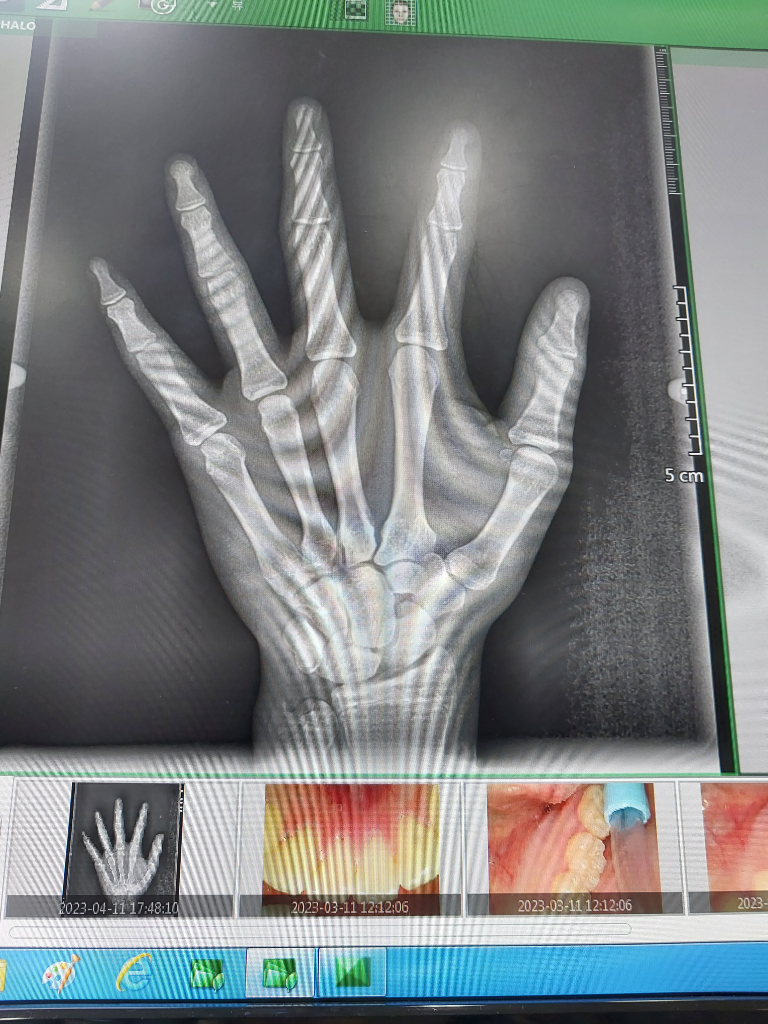

만나이:15세 입니다 밑에 있는 사진은 2023년 4월 11일에 찍은 오른쪽 손 x-ray 사진 입니다. 참고로. 현재 겨드랑이털 나고 있습니다,성기에 털이 나고 있고요 그리고 턱수염도 현재 나고 있습니다 그리고 유전적키는 얼마나 클수 있을까요? 부모님키 아버지:170cm 어머니:160cm 입니다 그리고 저의 현재키는 아침에 일어났을때에는 딱 170cm가 됩니다 그리고 저녁에 쟀을때는 168.8cm 입니다 제가 성장이 완료 됬을때에는 키가 얼마나 더 클수있을까요?